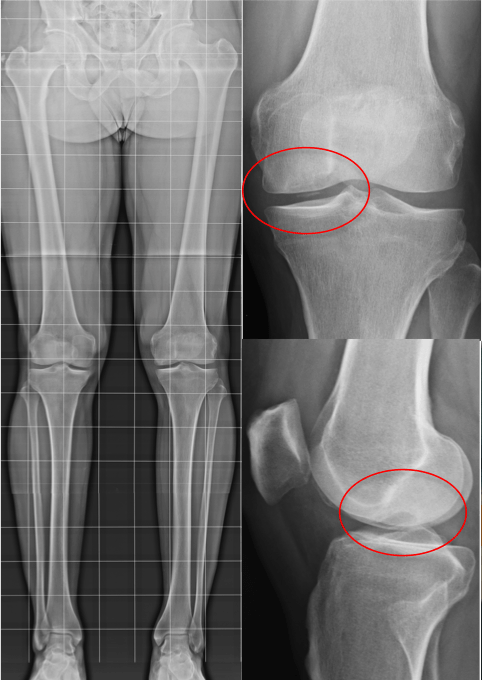

Il distacco parcellare della falange è un tipo di frattura che si presenta nel momento in cui un frammento dell’osso, fratturatosi a seguito di un incidente di natura traumatica, si distacca o si allontana dalla sua giusta posizione. Trattamento esiti di frattura diafisaria del iv metacarpo e distacco parcellare della base della falange prossimale del terzo dito. Uscii con le mie forze. Translate parcellare to english online and download now our free translation software to use at any time.

Distacco Parcellare M1. All'ospedale mi diagnosticarono un distacco parcellare al malleolo tibiale, e ovviamente la distorsione della caviglia. Il distacco parcellare della falange è un tipo di frattura che si presenta nel momento in cui un frammento dell’osso, fratturatosi a seguito di un incidente di natura traumatica, si distacca o si allontana dalla sua giusta posizione.

Distacco osseo parcellare del malleolo peroneale salve, sono una ragazza di 24 anni, circa un mese e mezzo fa.